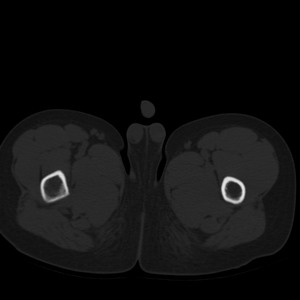

标题: PED1884:患者,男性,7岁。因右髋疼痛5天,而来院检查。 [打印本页]

标题: PED1884:患者,男性,7岁。因右髋疼痛5天,而来院检查。

因右髋疼痛5天,而来院检查。

我们考虑:1、骨皮质增厚症。2、畸形性骨炎。3、骨纤。

右髋疼痛,左侧病变,看来无症状。

支持左股骨上段骨纤维异常增殖症可能性大.